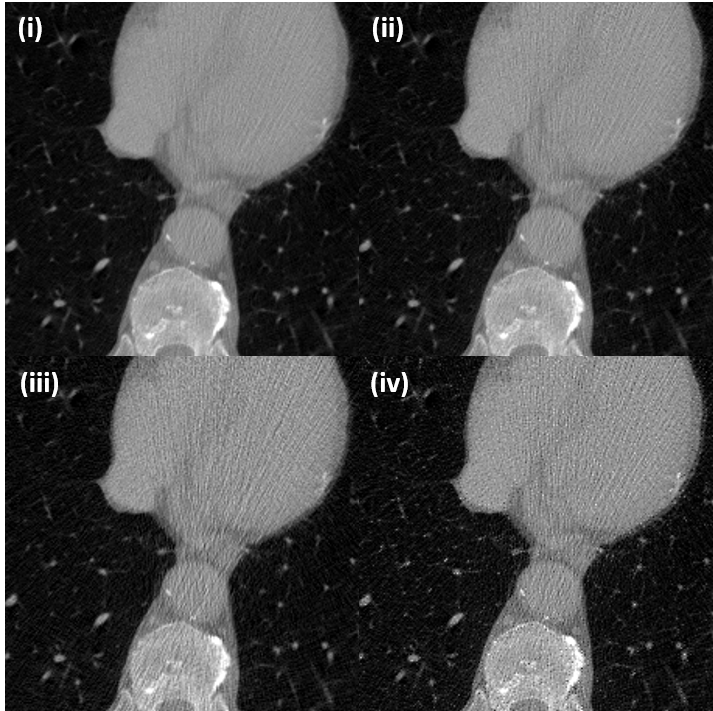

Fig. 9(a) shows representative denoising results by various methods. The resulting images are cropped at to more accurately visualize the denoising performance. The intensity of the CT images shown is (-1000, 1000) [HU] and the difference is (-200, 200) [HU]. Our CycleGAN with an invertible generator removes more noise components than the AdaIN-based CycleGAN method without losing any information. As can be seen from the Fig. 9(a), the proposed network (Fig. 9(a-iii)) removes noise components around high-intensity metals more evenly than AdaIN-based CycleGAN(Fig. 9(a-ii)).

To verify that the invertible generator can also properly perform the inverse mapping, we provide an inversely mapped output from SDCT images as shown in Fig. 9(b). The resulting images are cropped at resolution in order to more accurately visualize the improved quality. The intensity of the CT images shown is (-1000, 1000) [HU]. Even if the proposed method does not apply discriminator or loss for inverse mapping, the proposed method adds a reasonable level of noise to the SDCT, which makes the output of the LDCT appear closer than the AdaIN-based CycleGAN.